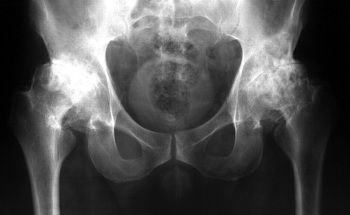

Prije dvije godine prvi put sam osjetila blage bolove u koljenima i kukovima. Bol nije bio jak, nisam posebno obraćala pažnju na to... Kako se pokazalo, bolesti zglobova su veoma ozbiljne i treba ih odmah liječiti, a ne odlagati kao ja! Jednog običnog dana osjetila sam ne baš jak, ali oštar bol u koljenima, a i kukovi su me ozbiljno počeli boljeti, mislila sam da je u redu, da će proći kao i uvijek. Kupila sam razne lijekove i masti i počela ih koristiti. Patila sam oko jednog tjedna , stanje mi se naglo pogoršavalo, bol je postao nepodnošljiv, počeo je akutni bol u kukovima, odlučila sam da se prvi put obratim ljekaru. Postavljena mi je ne jeftina dijagnoza, a moj ljekar je pogledao rezultate pregleda i rekao:

„Zašto ste ranije zanemarili simptome? Imate artrozu, artritis! Ako ne želiš da postaneš invalid, moraš hitno na operaciju kuka i koljena!"